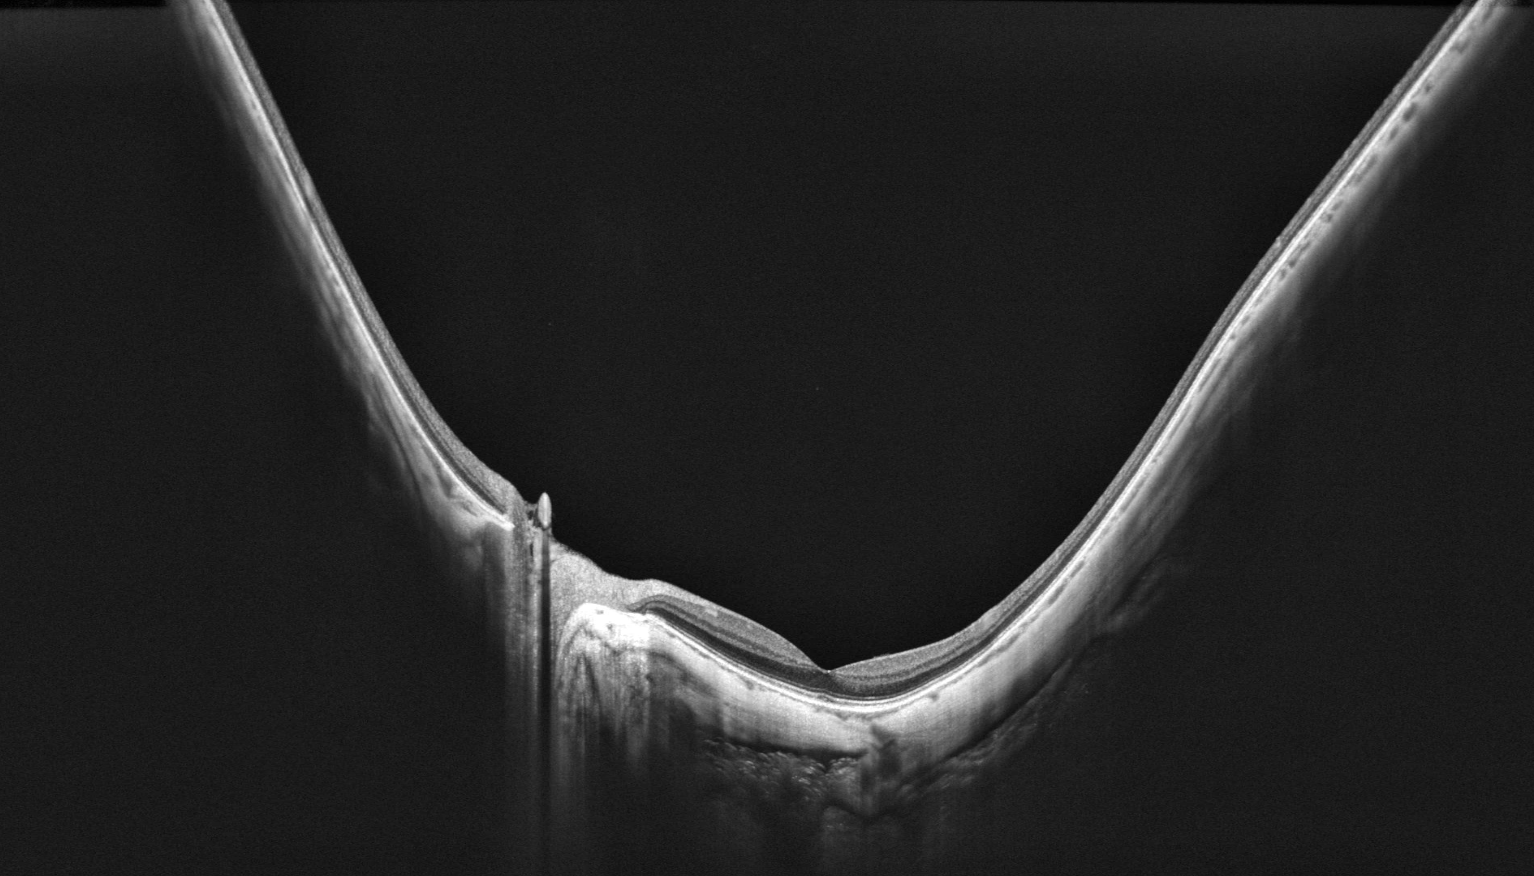

OCT montrant un staphylome myopique postérieur avec déformation du pôle postérieur et amincissement choroïdien

OCT grand champ — Staphylome myopique postérieur avec amincissement choroïdien marqué (IPO Paris)